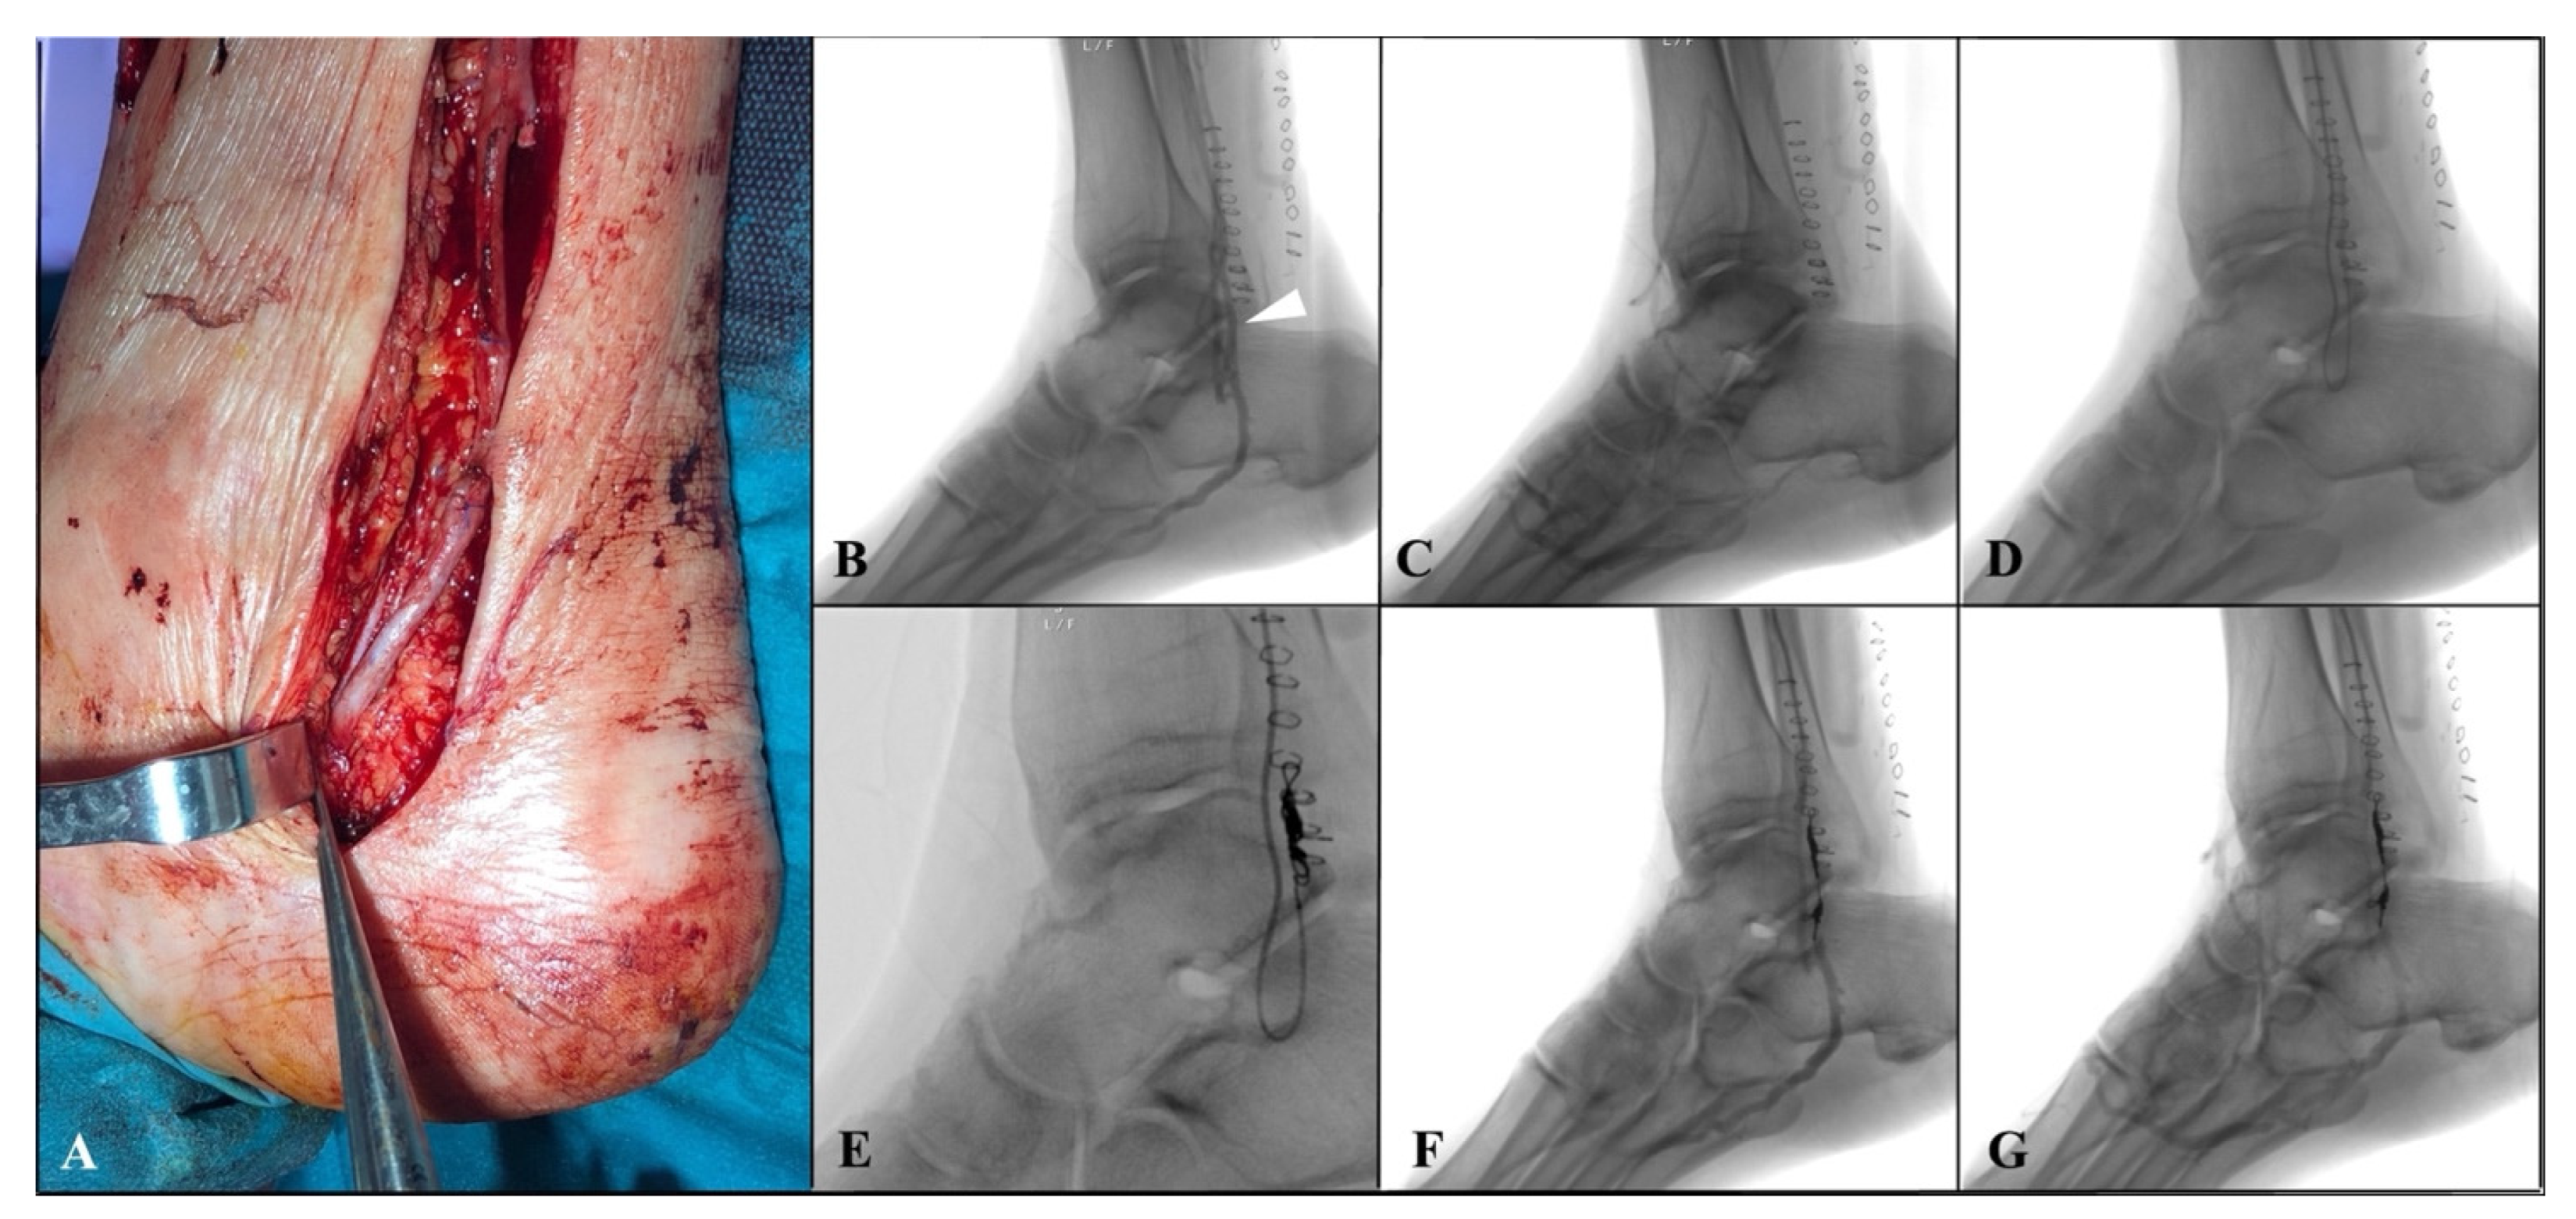

The distal anastomosis was then performed at the level of tibial vein in a termino-lateral fashion with a continuous 7/0 polypropylene suture (

Figure 2A). Then, the arterialized tibial vein is incompletely ligated using a 5/0 polypropylene distally to proximal anastomosis, partially reducing the blood theft from the foot. An intraoperative duplex scan examination was performed to assess the bypass’ patency.

® C1(Terumo, Somerset, NJ, USA), was advanced inside the vein graft, close to the distal anastomosis. Angiography was then performed to reveal the main venous collateral causing rapid wash-out of the contrast medium towards the leg, downstream of the distal anastomosis (

Figure 2B,C). Then, after crossing the distal anastomosis, a selective catheterization of the collateral was achieved using the Progreat

® microcatheter system (Terumo, Somerset, NJ, USA), and embolization of the vessel was performed by positioning a controlled-release spiral (Penumbra, Inc., Alameda, CA, USA) to implement distal perfusion of the foot. (

Figure 2D,G).

Three patients with pre-operative gangrene required minor amputations (

Table 2). In two patients, an open trans-metatarsal amputation was performed (

Figure 3), and in one patient, V finger amputation was performed.